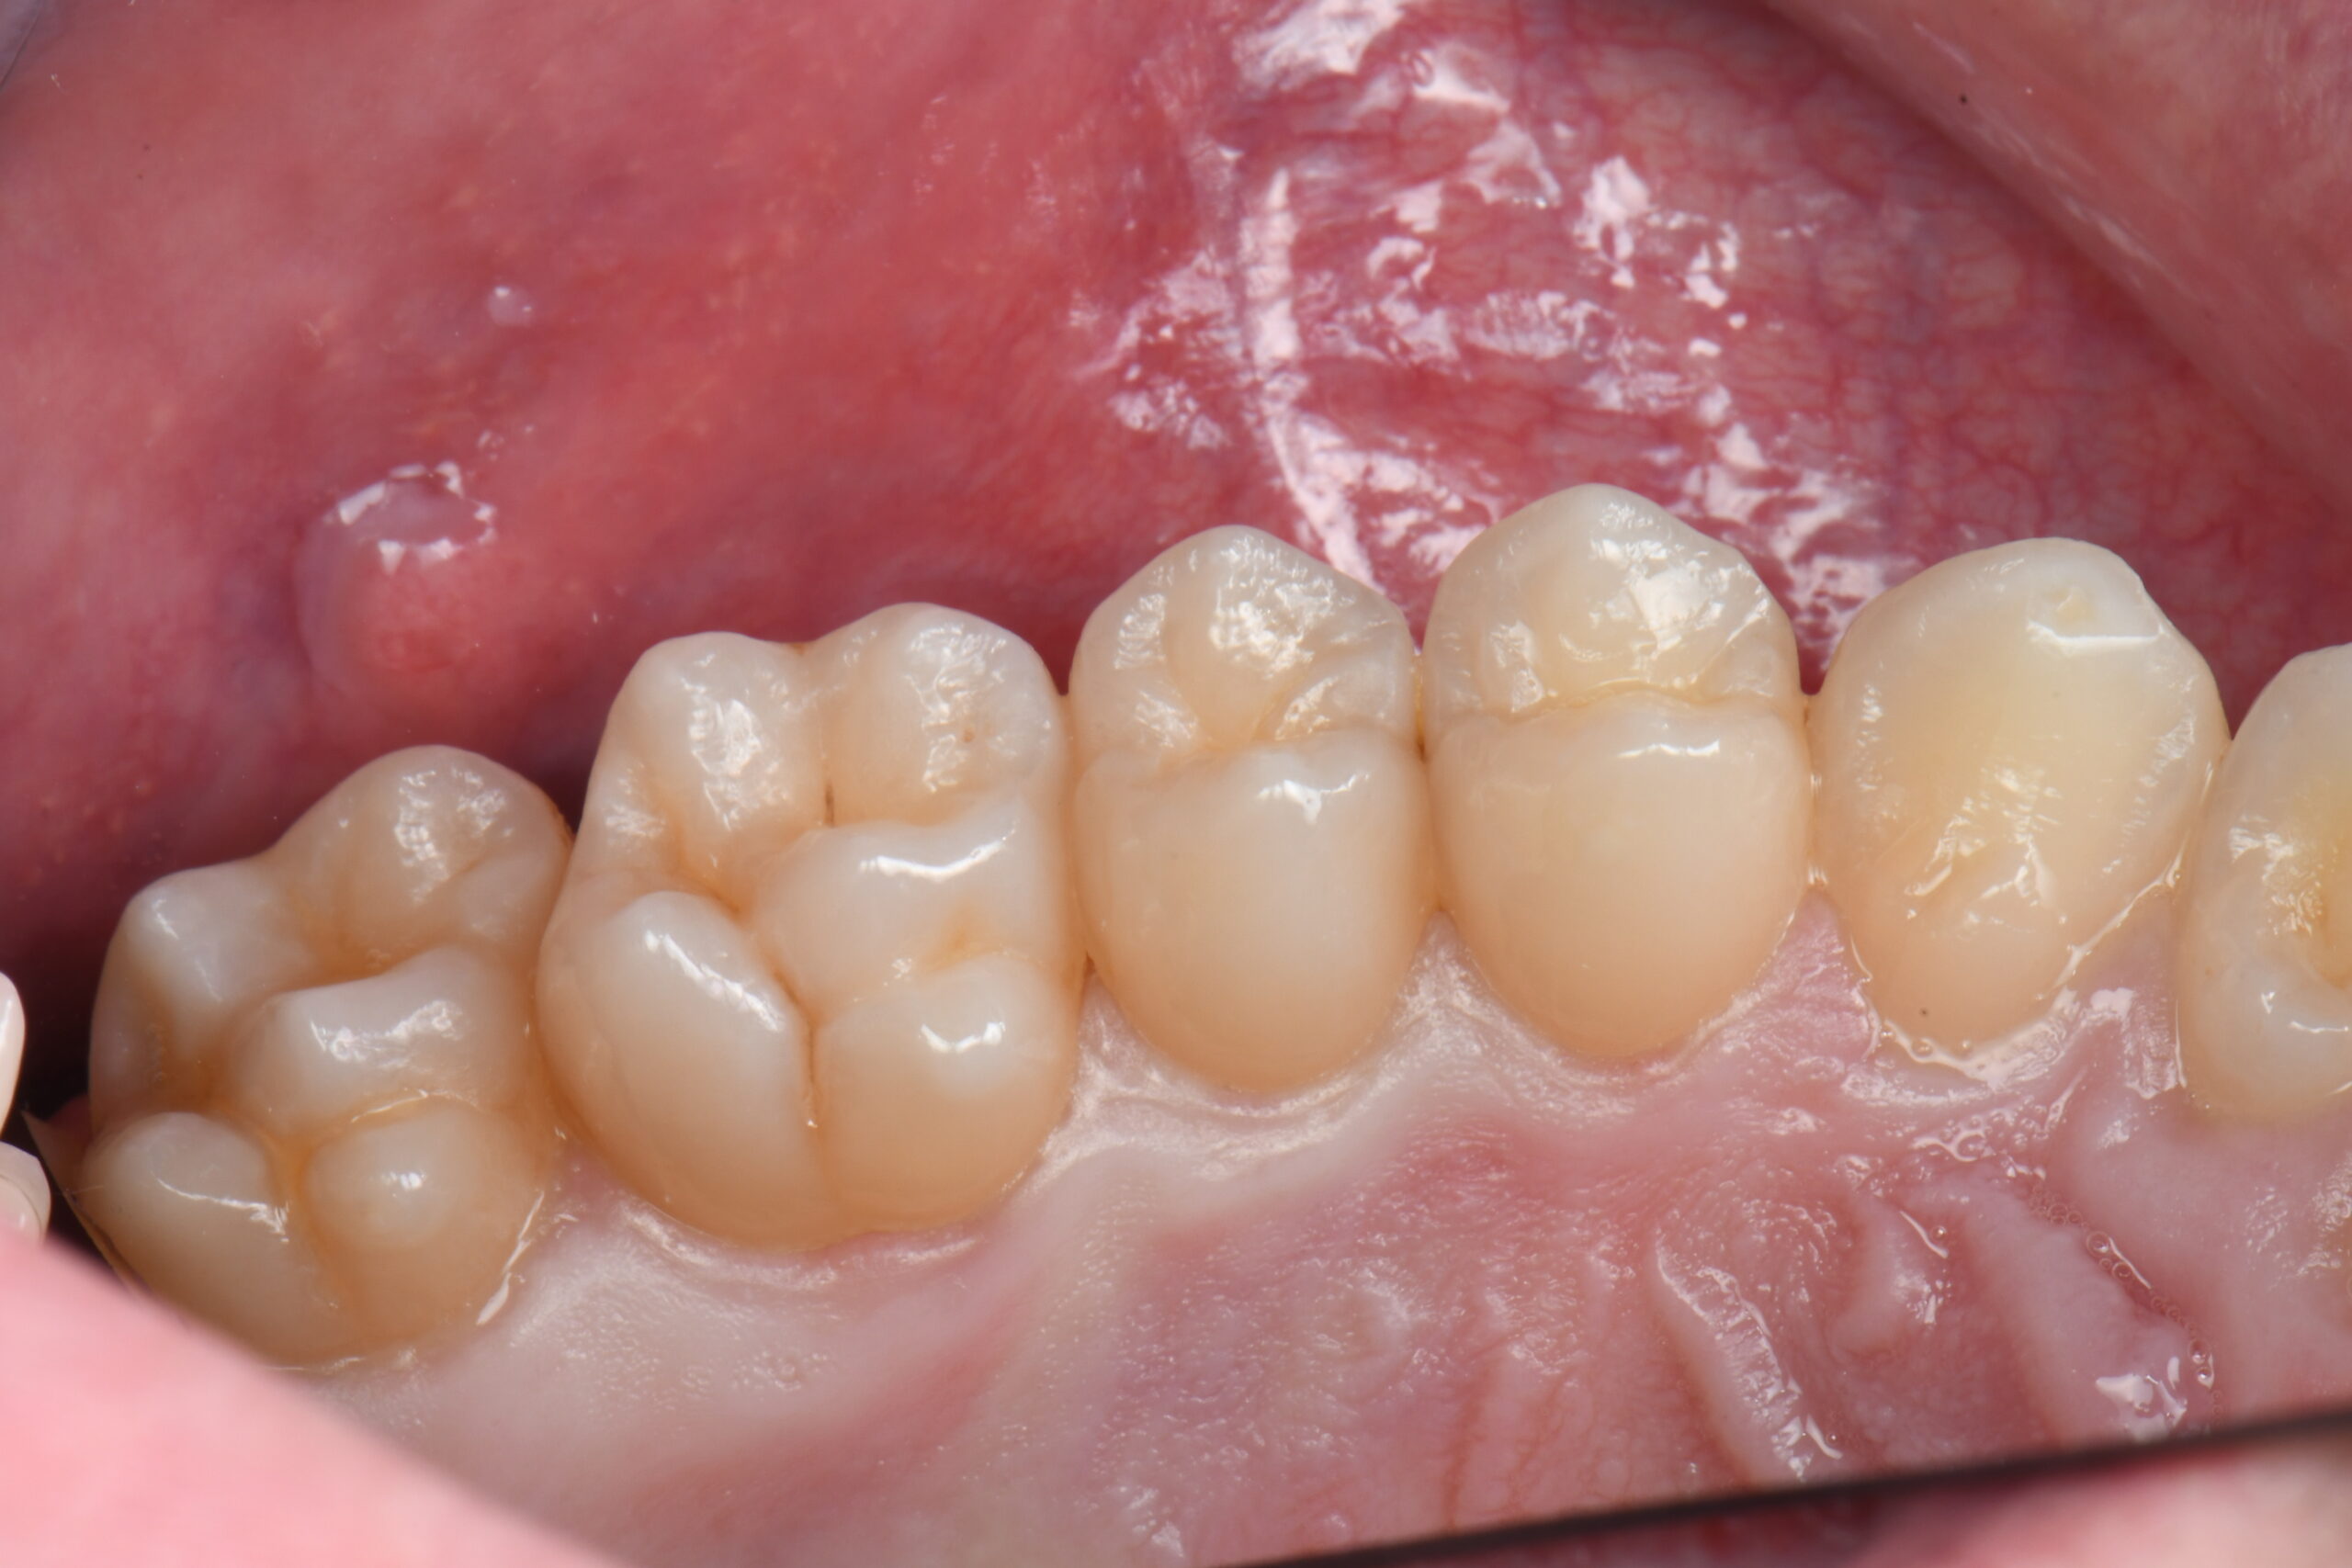

Close-up of six lower molars and premolars with visible occlusal surfaces and surrounding gum tissue

Immediate occlusal post-op photo after rubber dam removal and occlusal adjustments.